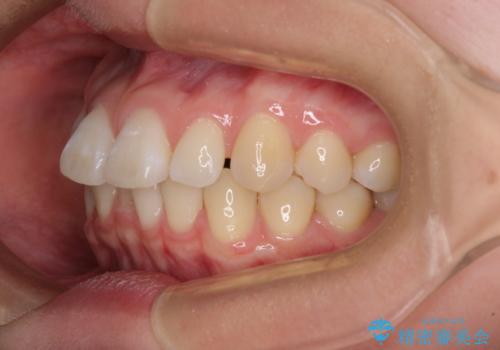

- 上顎前歯の隙間を気にして来院された患者様です。

下顎前歯が上顎前歯に食い込むような咬み合わせにより、上顎前歯が開いてしまっていたため、咬合高径の挙上により突き上げを改善するよう、インビザラインにより矯正治療を行うこととしました。

咬合高径の挙上により上顎前歯の突出感も改善することができ、整った口元となりました。